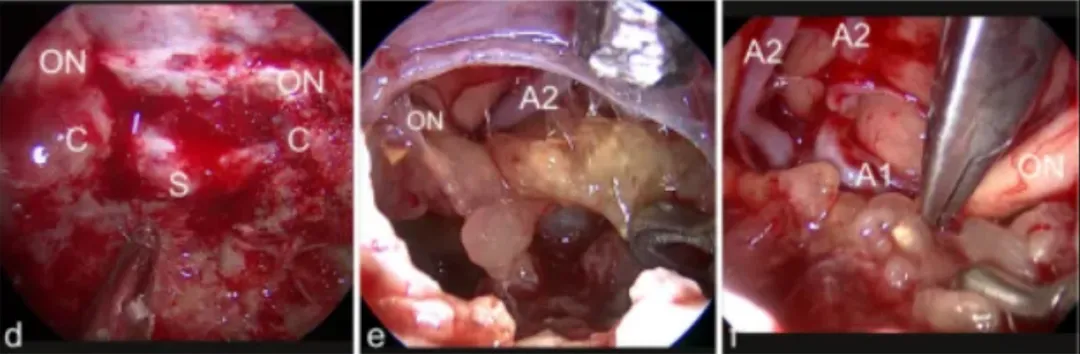

d图中,肿瘤(T)为通过右侧额外侧入路,暴露右视神经(ON)e图中,肿瘤包膜是用刀切开,f图显示钙化的肿瘤部分已被肿瘤切除

g图中,使用镊子的双向牵拉技巧解剖分离肿瘤;h图中,肿瘤(T)在30°神经内窥镜视野下正常显微镜难以显示;i图中,最终检查显示肿瘤全切除和视神经完整保留(ON)